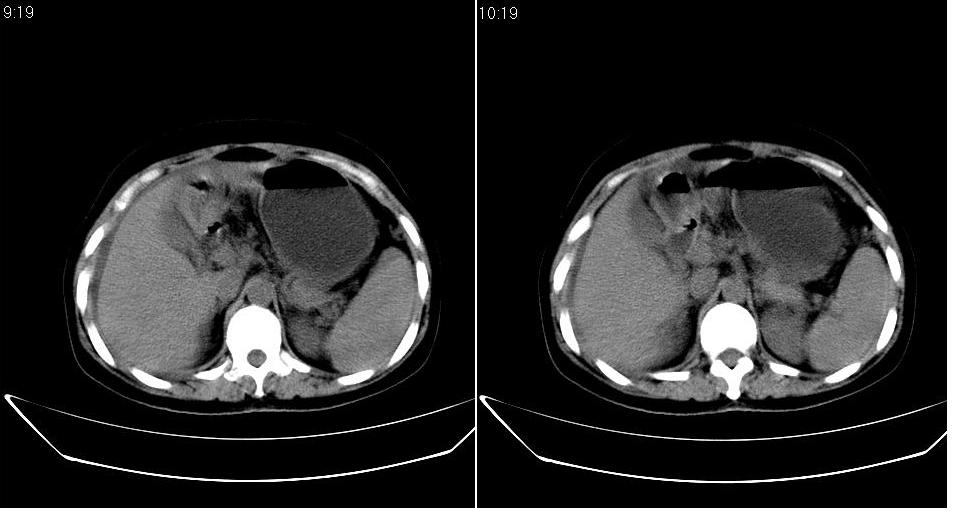

以下是引用zbp537在2009-1-19 14:09:00的发言:[br]从这个平扫图像上看,只能考虑:1、胸腹水。2、脾脏包膜下弧形高密度影,疑出血,建议复查。[br]既然腹水中有恶性细胞,建议行腹部ct增强扫描及胸部扫描。

以下是引用随光逐影在2009-1-19 15:47:00的发言:[br]1)不排除胃癌可能;建议行胃镜检查。2)腹水。3)右侧胸腔积液。

以下是引用jiangjing在2009-1-19 18:21:00的发言:[br]1 网膜污垢征---肿瘤网膜转移.2)腹水。3)右侧胸腔积液